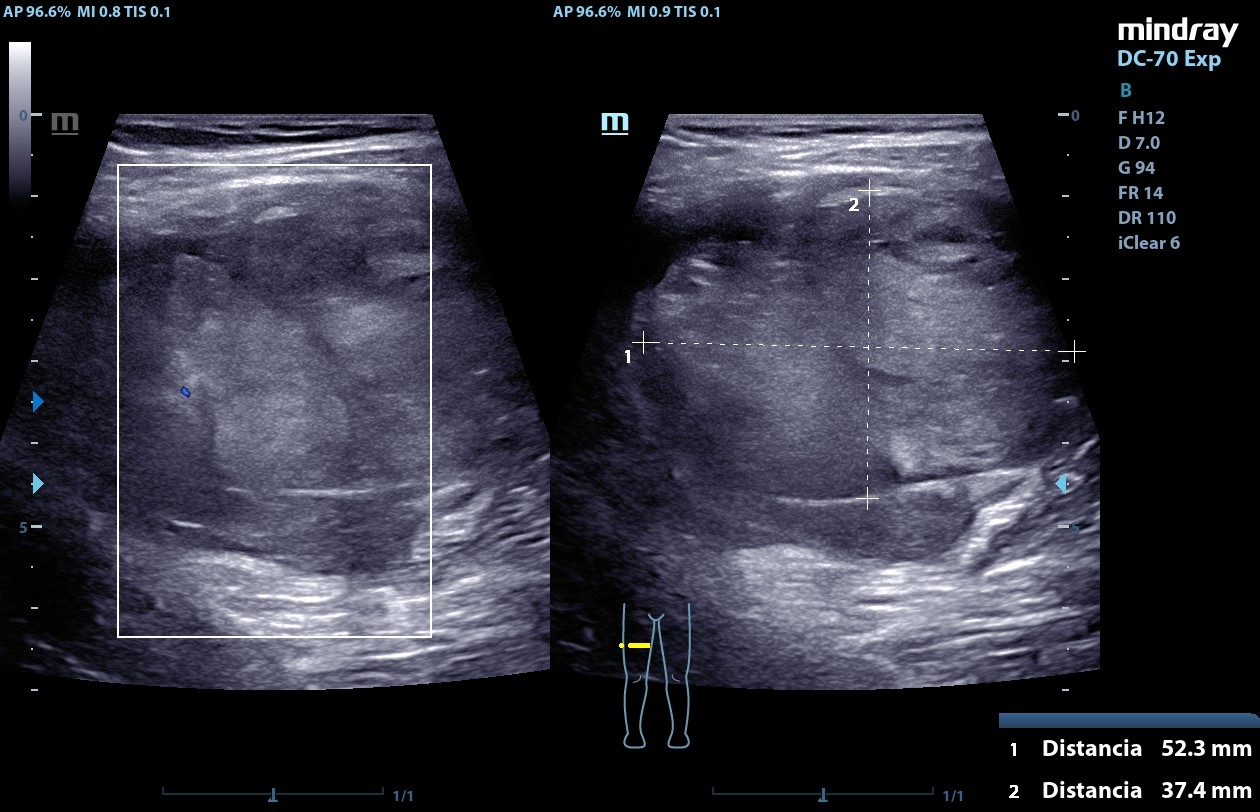

Ecografía POCUS (20/09/24): masa heterogénea de centro hiperecogénico, de bordes bien definidos, Doppler negativa de aproximadamente 52,3 mm x 37,4 mm x 67,3 mm compatible con neurofibroma plexiforme.